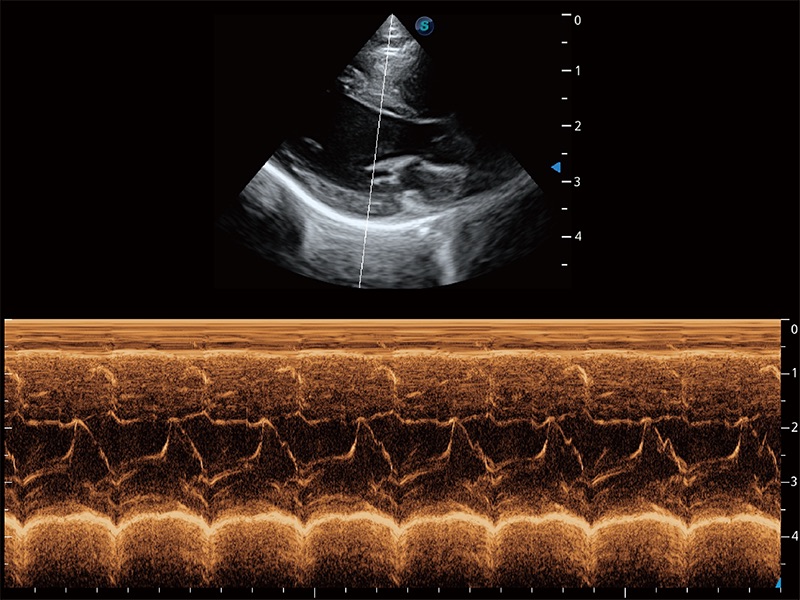

通过360度任意调节3条M型取样线,在同一心动周期上观察心脏不同位置的运动曲线,得到准确的心功能测量数据,有效评估心肌运动及左心室功能。

ProPet 80 配备了丰富的心脏探头群、先进的成像技术和专业的心脏测量工具,可帮助动物医生为不同体型和生理结构的动物提供心脏和心肌功能的全面评估。

实时用颜色表示心肌组织运动,观察和定量组织的运动情況,对快速检测与评估心肌的灌注和活性、电传导及心肌收缩和舒张功能等均能提供重要的诊断信息。